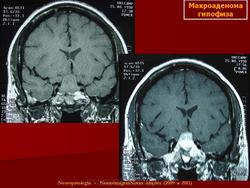

Аденома гипофиза.

Приложения:

1.ad_.slayd158.jpg2.ad_.slayd159.jpg